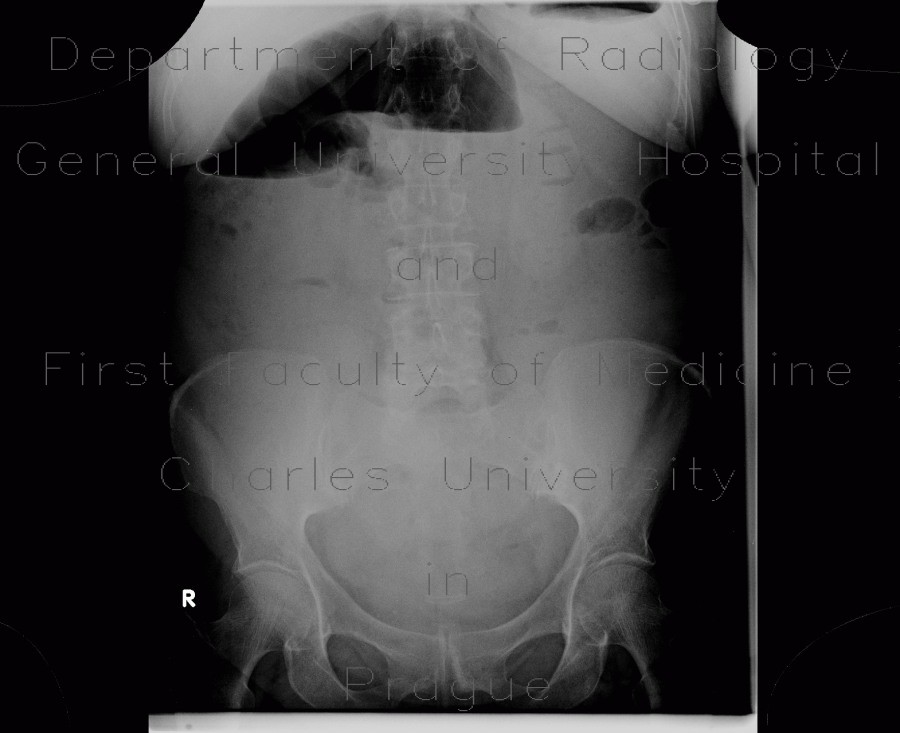

The most prominent finding in this examination was massive dilation of the colon with air-fluid levels indicating bowel obstruction (ileus). Its cause can be tracked down to sigmoid, where a tumorous thickening of the wall with extension into the mesosigmoid and involvement of local lymph nodes can be found. Small bowel loops remain relatively undistended thanks to competence of the ileocecal valve.